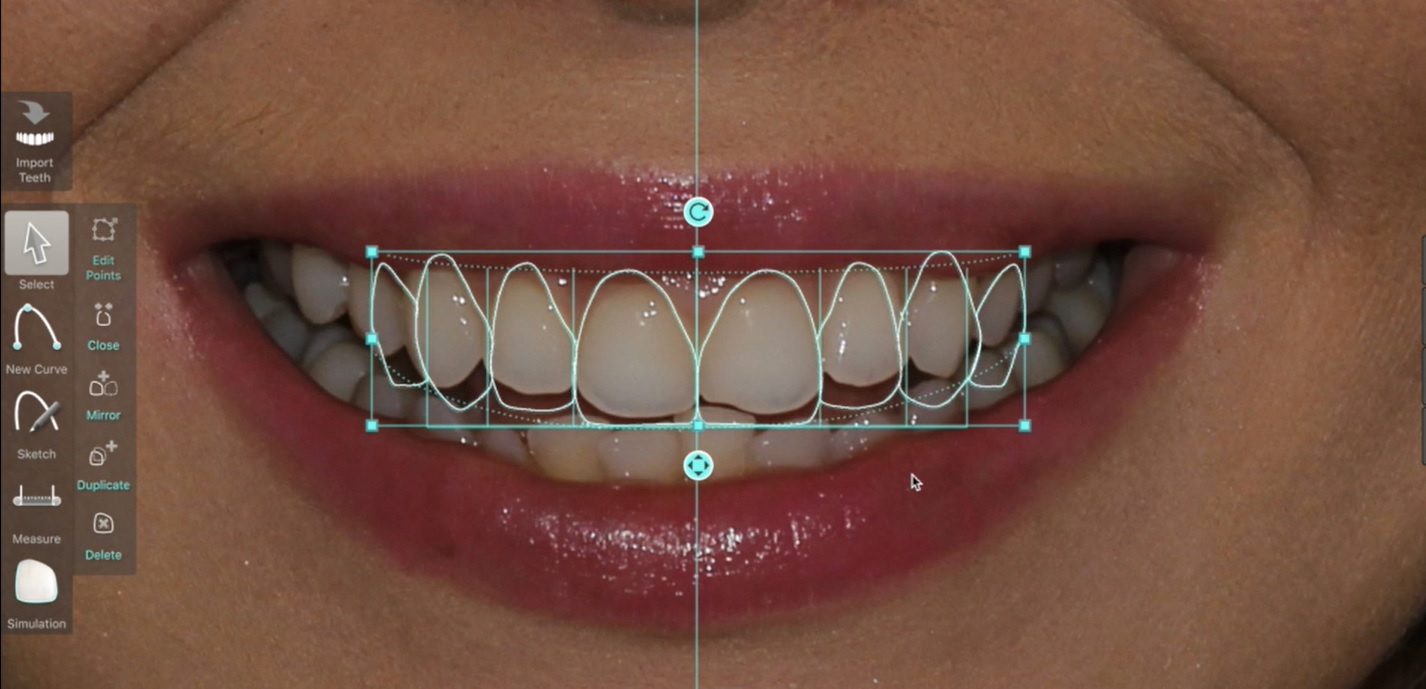

Belirlenen yeni diş yapısı ve dental oranlara göre gülüş tasarım yazılımı, planlanan tedavinin bitmiş halinin sanal görüntüsünü oluşturur. Bu görüntü üzerinde, hastanın da istek ve düşünceleri dikkate alınarak gerekli düzeltmeler yapılır.

Son hali verilen dijital gülüş tasarımı üzerinde dijital ölçümler yapılarak veya doğrudan Cad-Cam cihazlar kullanılarak dijital planlama , Mock-up adı verilen reel tasarıma dönüştürülür. Daha sonra, Mock-up tasarım, ağıza aktarılarak geçici dişler üretilir. Bu aşamada , yüz-dudak ve alt-üst dişlerin birbirleriyle uyumları ile diş renk ve boyutları, dişeti konturları detaylı olarak tekrar değerlendirilir. Bu değerlendirmeler sonrasında Mock-up üzerinde gerekli son düzenlemeler yapılıp protetik işlemlere geçilir. Bu iş akışı neticesinde elde edilen estetik sonuç, dijital tasarım ve Mock-up çalışması ile oldukça uyumludur.

Dijital Gülüş Tasarımı, pekçok farklı diş tipi ve renginin hastaya daha uygulanmadan bilgisayar ortamında denenmesi , hastanın görüşünün alınması , sonuç olarak da, hekimin ve hastanın beğenip onay verdiği tedavinin gerçekleştirilmesine imkan verir.